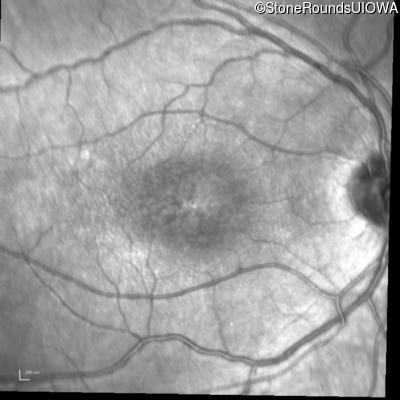

Infrared Fundus Photograph - Right - 20/63 -2

Exemplar

Infrared Fundus Photograph - Left - 20/50 -2